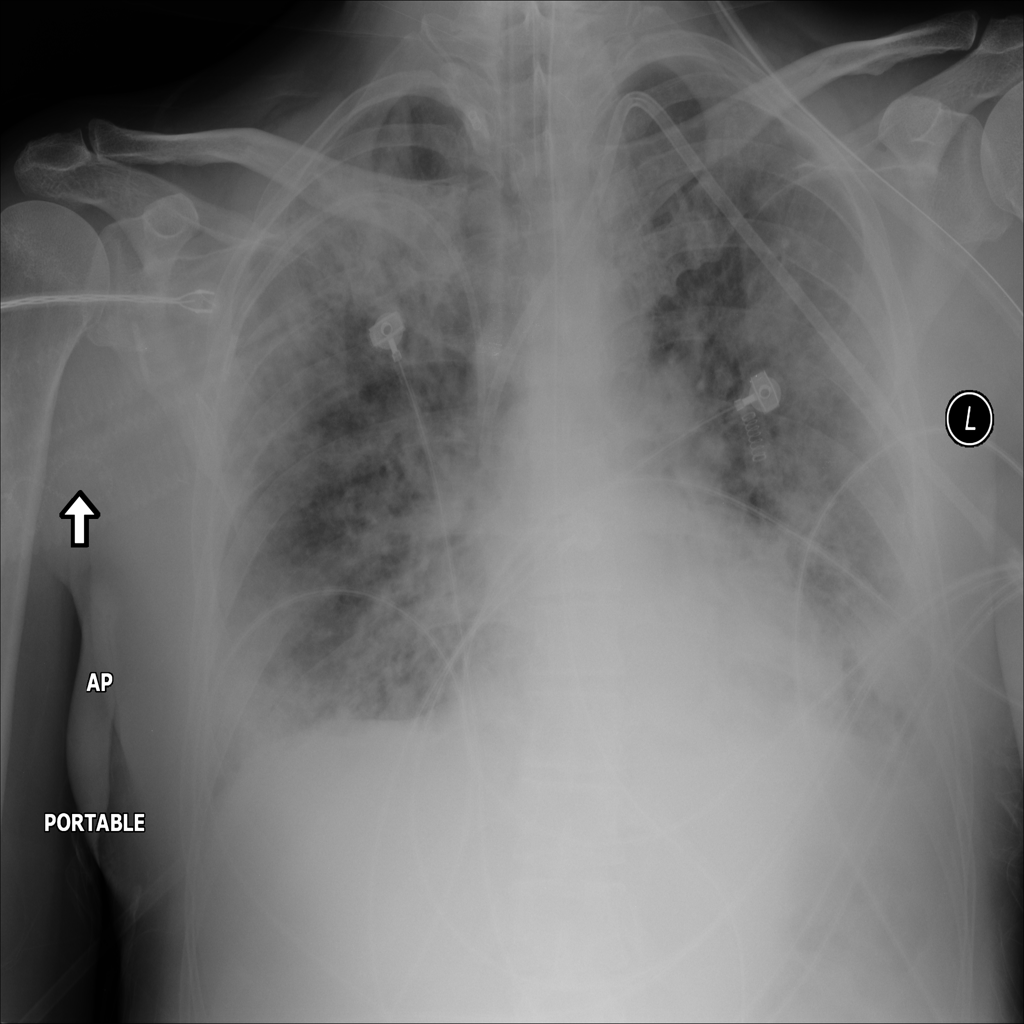

PAT-24D9 · IMG-006Edema

PAT-24D9 · IMG-006

AP